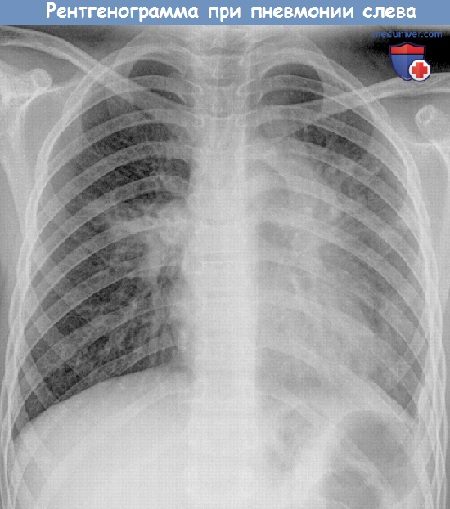

- Рентгенографическое исследование. Является основным методом диагностики пневмонии у детей. Позволяет определить воспалительный инфильтрат в лёгких, его локализацию, размер. Также с его помощью удаётся обнаружить скопление экссудата.

При пневмонии рентгенографическое исследование является наиболее информативным

Как определить, что у ребенка воспаление легких? Как правильно лечить пневмонию у детей?Воспаление лёгких — опасная болезнь, поэтому ее нужно уметь правильно лечить. Особенно это актуально по отношению к малышам, так как согласно статистике, каждый год во всем мире от пневмонии умирают 1,4 миллиона детей в возрасте до 5 лет. Несмотря на достижения современной медицины, воспаление легких по частоте смертельных исходов занимает первое место среди всех инфекционных заболеваний. Пневмония или воспаление легких — это инфекционное заболевание, при котором поражаются самые нижние отделы дыхательной системы и нарушается функция легкого. Именно поэтому основным показателем пневмонии является не кашель и насморк, а одышка, потому что альвео-лярные мешочки при воспалении легких наполняются жидкостью или гноем, что затрудняет газообмен и вентиляцию в легких. Частое и кряхтящее дыхание ребенка — серьезный повод для обращения к врачу, даже если насморка и кашля при этом у него нет. В норме частота дыхания у детей в спокойном расслабленном состоянии должно быть следующим: — у новорожденных младше 2 месяцев — до 50 вдохов в минуту; — у малышей от 2 месяцев и до 1 года — до 40 вдохов в минуту; — у детей в возрасте 1-3 лет — до 30 вдохов в минуту; — у дошколят в возрасте 3 -7 лет — до 25 вдохов в минуту; — у школьников 7 -10 лет — до 20 вдохов в минуту. При воспалении легких эти показатели намного больше. Заболеть пневмонией ребенок может в любое время года, а не только зимой. Особенно опасна пневмония для малышей до 5 лет, иммунитет которых еще неокрепший, а организм их еще не умеет справляться с инфекцией. Пневмония редко бывает самостоятельной болезнью, чаще всего она развивается на фоне бронхита, сильной простуды и заболеваний горла из-за загустевания и плохого отхождения мокроты, препятствующей вентиляции легких. Причиной развития воспаления в легких могут быть вирусы, бактерии и грибки. Встречаются и смешанные воспаления, например, вирусно-бактериальные. По степени развития болезни пневмония может быть односторонней и двусторонней. Двусторонняя пневмония наиболее опасная, именно она является основной причиной детской смертности. К сожалению, многие родители ошибочно принимают пневмонию ребенка за обычную простуду и ждут, когда вот-вот ему станет лучше. И только тогда, когда ребенок уже становится сосвсем слабым, а его температура не падает даже после приема жаропонижающих средств, вызывают скорую помощь. Важно: если у ребенка высокая температура, он жалуется на боль в груди при кашле и дыхании, у него одышка, то обязательно надо вызвать врача, чтобы исключить воспаление лёгких. Специфические симптомы, по которым можно заподозрить пневмонию у ребенка, следующие: — он болеет гриппом или другой вирусной инфекцией уже 3-5 дней, а состояние его не улучшается или после незначительного улучшения температура поднялась снова; — жаропонижающие средства малоэффективны, они сбивают температура лишь на 30-40 минут ; — у него частое и шумное дыхание, одышка; — он часто кашляет, попытки сделать глубокий вдох каждый раз заканчиваются кашлем; — он слабый, постоянно спит и ничего не хочет кушать; — кожа у него стала бледной, а губы приобрели синюшный оттенок; — он жалуется на боль в животе и тошноту. Для диагностики пневмонии врач прослушивает дыхание ребенка стетоскопом, дает направление на сдачу анализа крови и прохождение рентгента грудной клетки. При пневмонии прослушиваются хрипы влажные и мелкопузырчатые, а при бронхите они сухие и свистящие. В последнее время для точной постановки диагноза «пневмония» терапевты используют результаты анализа крови на С реактивный белок. По результатам такого исследования можно определить, насколько сильно воспаление в легких. Если уровень С реактивного белка меньше 20 мг/л, то, скорее всего, у ребенка — бронхит, а воспаления в легких нет. Если же этот показатель приближается к 100 мг/л, то надо срочно сделать рентгеновский снимок, чтобы окончательно подтвердить диагноз «пневмония». Рентгенограмма при пневмонии у ребенка. Рентгеновский снимок — обязательный метод исследования при подозрении пневмонии (воспаления легкого). Лечение пневмонии зависит от типа микроорганизма, который способствовал ее развитию. Вирусная пневмония, которая развивается на фоне ОРВИ, считается более легкой формы. Она не требует длительного лечения и обычно проходит вместе с вирусной инфекцией. Чего нельзя сказать о бактериальной пневмонии. Ее обязательно следует лечить антибиотиками. Они помогают не только бороться с инфекцией, но и снижают температуру. Поэтому в данном случае жаропонижающие средства врач может и не назначить. Многие родители спрашивают врачей: «А можно ли лечить пневмонию ребенка дома?», так как не желают оставлять его одного в больнице. Биодоступность современных антибиотиков высокая, поэтому при легких формах пневмонии врач может разрешить лечить ребенка и дома, но отказываться от госпитализации, пренебрегая врачебных рекомендаций, при воспалении легких нельзя. Особенно если родители несвоевременно вызвали терапевта и пытались лечить ребенка сами, успев дать ему попробовать 2-3 вида антибиотика. В этом случае понятно, что таблетки ребенку уже не помогут, надо делать инъекции. Начатое на ранней стадии лечение воспаления легких помогает избежать тяжелых осложнений. Очень распространённая ошибка многих родителей — самостоятельно прекращать давать ребенку антибиотики. Полечились 3- 5 дней, температуры больше нет, и перестают давать лекарства, назначенные врачом. Этого делать ни в коем случае нельзя. Если врач назначил курс антибиотиков на 10 дней, значит, принимать их нужно именно столько времени, и ни днём меньше, даже если ребенок чувствует себя уже здоровым. Во время болезни ребенок отказывается от еды и не хочет пить. Это нормальное явление, указывающее на то, что организм «экономит» силы, чтобы бороться с недугом. Заставлять ребенка насильно кушать не нужно, а вот поить его водой надо часто и небольшими порциями. Она разжижает слизь в легких и выводит токсины из организма. Вместо воды можно ребенку дать настой шиповника, компот из сухофруктов и ягод, а также свежевыжатые соки, разбавленные водой 1:1. В период лечения пневмонии не нужно давать ребенку аптечные общеукрепляющие витаминные или иммуномодулирующие препараты. Они только увеличивают нагрузку на печень, которая во время болезни и так страдает. После окончания приема антибиотиков врач может назначить пробиотики, восстанавливающие микрофлору кишечника, сорбенты, чтобы ускорить очищение организма от токсинов и витаминное питание. В комнате, где лежит больной ребенок, должно быть чисто и свежо. Полезно там поставить увлажнитель воздуха, чтобы мокроты не пересыхали и не застаивались в легких, а ребенку было легче дышать. При правильном лечении пневмонии ребенок быстро восстанавливается. К нему возвращаются прежний аппетит, отличное самочувствие и хорошее настроение. Видео уроки техники аускультации легкихРекомендуем посмотреть другие видео ролики по пропедевтике Предлагаем ознакомиться со звуками аускультации легких:1. Везикулярное дыхание: 2. Бронхиальное дыхание: 3. Влажные хрипы: 3. Сухие хрипы: 4. Шум трения плевры: 5. Крепитация: 6. Жесткое дыхание: 7. Амфорическое дыхание: 8. Побочные дыхательные шумы: 9. Аускультация легких: — Вернуться в оглавление раздела «Пульмонология» Автор: Искандер Милевски Рекомендуем ознакомиться с тематичными статьями на нашем сайте: